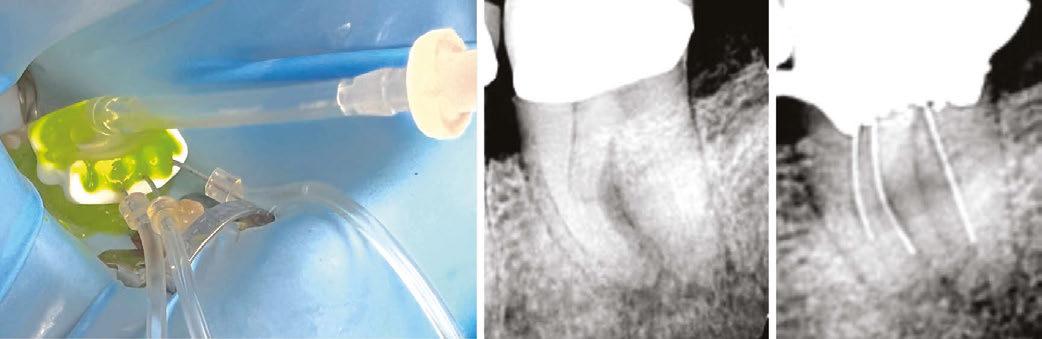

Figure 2 (left): PulpSucker Irrigation device with its stage, manifold, and supply lines feeding catheters placed to midroot in each canal, and its vacuum port exiting the top plate of the stage. Staging is a 3-minute procedure after which PulpSucker Irrigation runs by itself. Figure 3 (center): Preoperative radiography of this irreversibly inflammed mandibular molar shows incipient lucencies at both root apices and in the furcation between the roots. Figure 4 (right): PS cannulas in place 3 mm-5 mm short of the canal terminus

Figure 5 (left): The immediate post-op radiograph revealing a mid-root mesial canal exiting into the furcal lesion and a multiplicity of apical lateral canals in both roots. Figure 6 (center): Axial CBCT slice showing the mid-mesial canal filled into the center of the mid-root pathosis. Figure 7 (right): 3-month recall showing complete regeneration of periradicular bone adjacent to the lateral ports of exit

Case report

Figures 3-7 show a lower molar treated with PulpSucker Irrigation after instrumenting the mesial canals to a 20-.03 shape and the distal canal to a 25-.05 shape. Obturation was accomplished with bioceramic sealer and the Continuous Wave filling technique.

Why are we so thrilled when we see lateral anatomy filled in our post-op radiography? It’s because 3D obturation of lateral recesses is a proxy for our irrigating efficacy. If you have not cleaned a lateral canal during irrigation procedures, you are not going to see it filled afterwards. Conversely, when several lateral canal projections are seen after treatment is finished, we can give ourselves a pat on the back for doing a thorough job of irrigation. This is no small accomplishment, especially in light of the recent trend toward minimally invasive endodontic procedures. In fact, MIE concepts and procedures up the ante of our mission to clean these uninstrumentable parts of root canals, and in fact, enhanced irrigation methods that produce cavitation have played a serious part in driving this trend (Figure 9). This case shows how really complex endodontic anatomy can

Figure 8: Close-up views of the apical two-thirds of the roots. The mid-mesial canal is 6 mm long; preoperatively, it contained vital pulp tissue, and it was never touched with a file, yet it has been definitively treated by PulpSucker Irrigation. Note the four lateral canals in the apical 2 mm of the roots, again, never touched by a file. Cavitation rocks

Figure 9: Mandibular molar treated with PulpSucker Irrigation through three independent MIE access openings. Note the apical delta system of lateral and accesssory canals in the apical third of the distal root. No dentin was cut in this canal by instruments, yet PulpSucker Irrigation was able to clear out the 5-7 portals of exit. This took 5 minutes to stage and catheterize, then ran by itself for the 15 minutes it took to run 100 mls of sodium hypochlorite through this super-complex root canal system